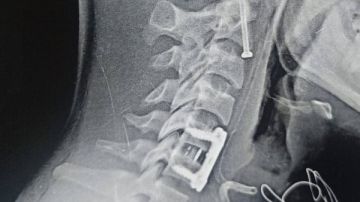

وكان قسم الاستقبال والطوارئ بمستشفيات جامعة بنها قد استقبل المريض عقب سقوطه من علو، وبالفحص والأشعة تبين إصابته بكسر في الفقرة العنقية الثانية، وهي من أكثر المناطق خطورة لقربها من جذع المخ المسؤول عن الوظائف الحيوية، إضافة إلى وجود تزحزح فقاري بين الفقرتين الخامسة والسادسة.

وأُجريت الجراحة تحت إشراف وتوجيه الدكتور إسلام أبو الفتوح رئيس قسم جراحة المخ والأعصاب، والدكتور إيهاب سعيد رئيس قسم التخدير، حيث تمكن الفريق الطبي من تثبيت كسر الفقرة العنقية الثانية بدقة عالية، إلى جانب تثبيت التزحزح الفقاري بين الفقرتين الخامسة والسادسة باستخدام شريحة ومسامير وقفص عنقي.